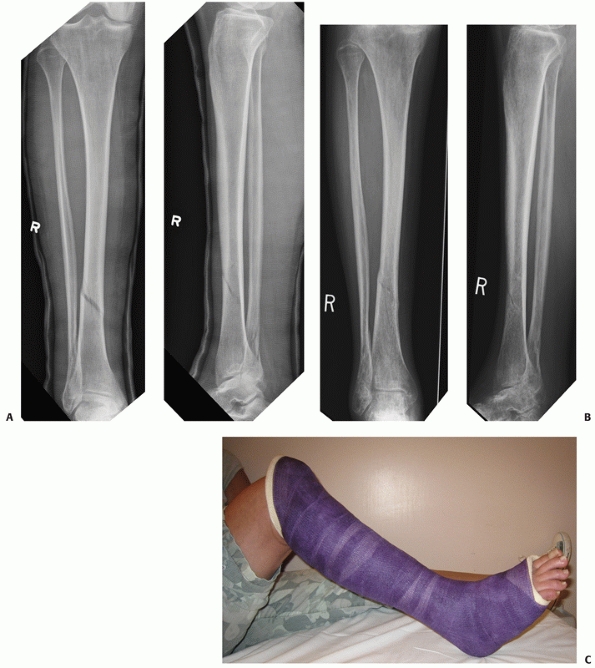

![]() |

FIGURE 55-8 A. An OTA A1.3 undisplaced stable distal tibial diaphyseal fracture that was treated nonoperatively. B. Weight bearing was started at 4 weeks and was full at 6 weeks. Union was uneventful. C. A long leg cast was used for 4 weeks followed by a patellar-tendon bearing cast as shown here.